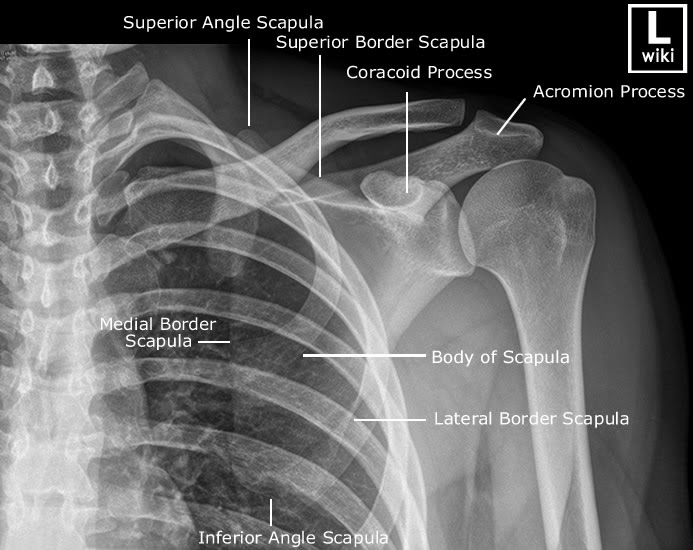

Scapula Anatomy Xray Ct Anatomy Of Scapula The scapula is a flat triangular bone with several distinct regions (fig. The scapula forms the posterior of the shoulder girdle. Normal ct shoulder for reference. The scapula is a set of radiographic images used to evaluate the scapula and surrounding structures. The glenoid fossa forms the articular surface of the scapula and connects to the scapular. The function of. Ct Anatomy Of Scapula.